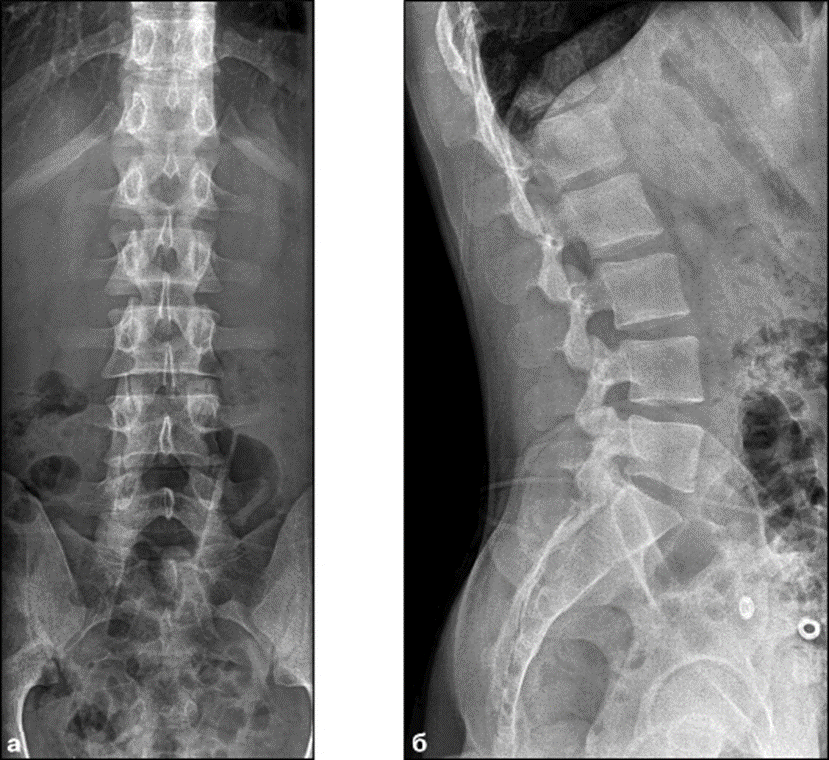

Рентген

Это оптимальный метод диагностики, когда речь идет об обследованиях костных структур. С его помощью определяются искривления позвоночника, компрессионные переломы и другие патологии позвонков. Но на снимках недостаточно ясно видны хрящевые и мягкие ткани. Говорить о точном диагнозе сложно.

-2